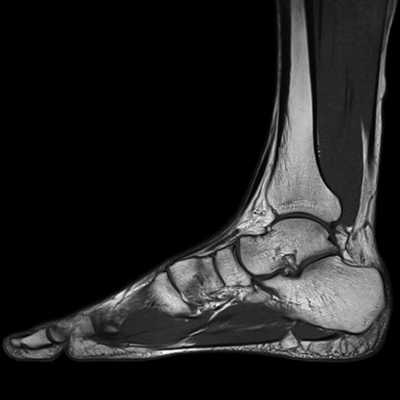

- МРТ голеностопного сустава и стопы позволяет хорошо рассмотреть эту область, так как рентген часто не выявляет проблему (не позволяют оценить состояние окружающих мягких тканей). На МРТ стопы хорошо просматриваются сухожилия, связки, суставы предплюсны и т.д. Можно видеть толщину и состояние хрящей, наличие выпота внутри суставов, крови, отек тканей, опухоли. Диагностируют пяточную шпору, болезнь Севера, подошвенный фасциит, плоскостопие, врожденные аномалии развития, нарушение кровоснабжения, опухоли, воспалительные, дегенеративные процессы, инородные тела в этой области, диабетическую стопу.

приходится до 25% от общего количества травм опорно-двигательного аппарата и 40-60% от числа повреждений нижней конечности. Диагностировать патологии области сочленения ноги и ступни можно с помощью рентгена, КТ и МРТ. Данные рентгенографии и компьютерной томографии в большей степени сфокусированы на визуализации костных тканей. Магнитно-резонансная томография явилась методом комплексной оценки повреждений голеностопного сустава и стопы. Её чувствительность в диагностике травматических повреждений и дегенеративных патологии в среднем составляет 98%, специфичность - 89%, точность - 94%. МРТ голеностопа позволяет получить четкие послойные снимки костей голеностопного сустава, хрящей, связочного аппарата, сухожилий, сосудов и окружающих их мягких тканей.

Что видно на МРТ голеностопа?

В ходе томографии голеностопного сустава оцениваются следующие анатомические аспекты:

- Взаимоотношения суставных поверхностей в голеностопном суставе и выпот стопы.

- Состояние подтаранного сустава.

- Проверяется, что медиальная и латеральная лодыжки не повреждены. Сухожилия задней и передней большеберцовых мышц, длинного сгибателя пальцев, длинной и короткой малоберцовых мышц не изменены или воспалены.

- Нет ли деформации и воспаления по ходу сухожилия задней б/берцовой мышцы.

- Дельтовидная связка носит целостный характер.

- Перонеальный удерживатель сухожилий не изменен.

- Передняя и задняя межберцовые связки не повреждены, щель межберцового синдесмоза равномерна и не расширена.

- Передняя малоберцово-таранная связка не определяется за счет отрыва от наружной лодыжки.

- Задняя малоберцово-таранная связка утолщена и разволокнена за счет растяжения и определяется на всем протяжении.

- Задний край таранной кости не деформирован.

- Пяточное (Ахиллово) сухожилие без патологических особенностей. Подошвенная фасция равномерно утолщена, а тарзальный канал не изменен.

- Собственно голеностопный и подтаранный суставы не деформированы.

- Мышцы не деформированы и однородны по интенсивности МР-сигнала.